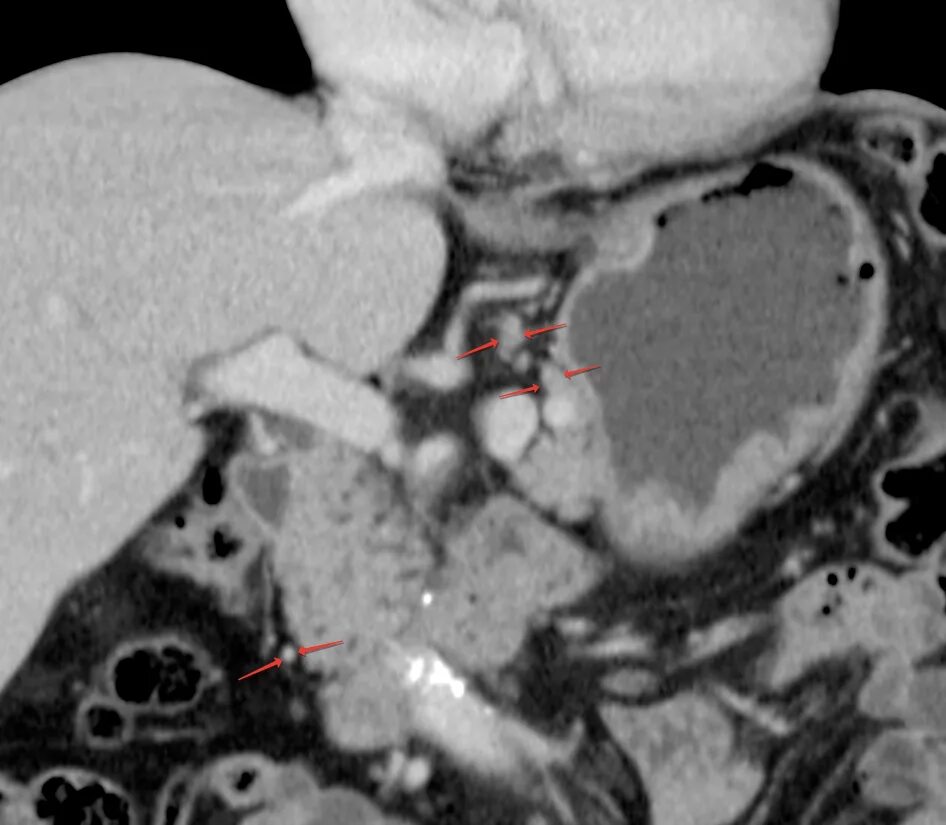

Язва желудка кт